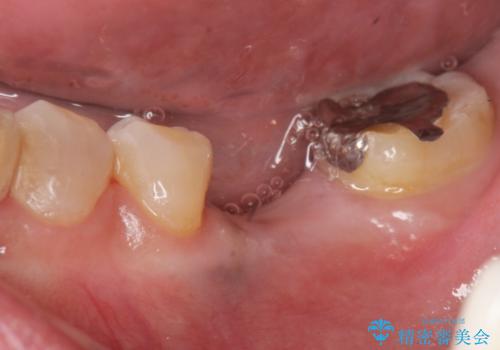

奥歯が割れている 抜歯してインプラントへ 40代女性

![[ 2歯連続欠損 ] インプラントによる機能回復 の症例 治療前](https://seimitsushinbi.jp/wp/wp-content/uploads/2021/06/7619f7b5c1f1e4edf6d576f5ab41abe7-500x350.jpg?v=1623390638)